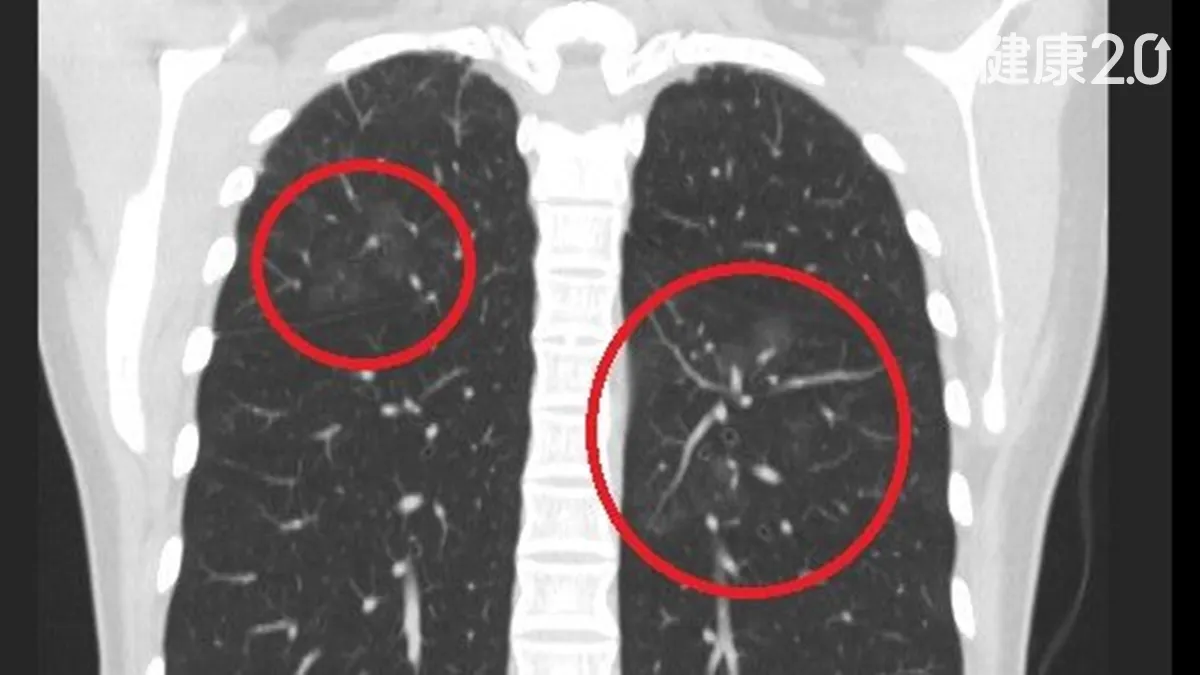

擔心肺癌照X光保平安沒用!他每年照 會喘才驚見「滿天星」

...科醫師蘇一峰提醒,想用X光檢查有沒有肺癌並不準確,還是應該做低劑量電腦斷層掃描(LDCT)。 老菸槍逃避照LDCT 發現肺癌已成末期台北市...